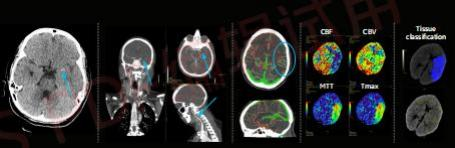

急性脑梗塞患者,全脑灌注扫描仅需5分钟

APEX CT在临床应用中聚焦目前对人类健康威胁最大的心脑血管疾病和肿瘤疾病,可以做到冠脉、全身血管的超早期肿瘤一站式扫描,且每一次扫描都能获得以往CT设备无法比拟的高清图像质量,最大程度的保留了图像的真实纹理、解剖结构和病理细节,实现了低剂量、低噪声和真实图像纹理的三位一体。

在世界卫生组织公布的全球十大致死病因中,心血管疾病常年处于首位。APEX CT可以开展头颈心联合扫描,对排查早期斑块,提前预防斑块脱落造成的脑部血管阻塞具有重要意义。心脏每分每秒都在运动,如何能够在快速的运动中,得到稳定且清晰的图像?心脏CT扫描一直是难点,常规的心脏CT检查需要一套复杂的流程,患者常常需要先服用控制心率的药物,还需要进行屏气训练,儿童患者还需要进行镇静……而对于高心率、心律失常、无法屏气和需要介绍全身血管扫描成像的患者,CT扫描更是难上加难。